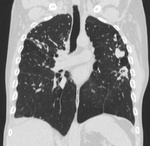

Пациент, впервые заболел в 02 году в ЗК, после рецидив в 07, потом в 11году. Сейчас состоит по активной группе с диагнозом: ФКТЛ легких , 1А (-)ГДУ. А по КТ оказалось, что все и не плохо.

Кроме ФКТ, думаю, что ещё и множество туберкулём. Или это очагами называете? Если туберкулёмы, то в 6-ке справа похоже на распад.